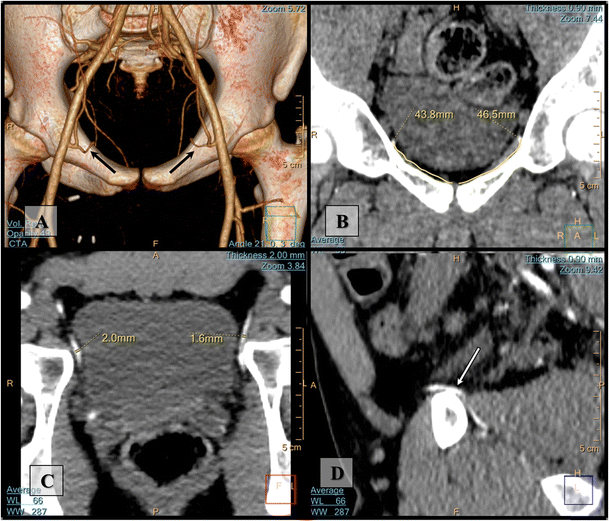

Importance Of Both Internal And External Iliac Artery Interrogation In Pelvic Trauma As Evidenced By Hemorrhage From Bilateral Corona Mortis With Unilateral Aberrant Origin Off The External Iliac Artery